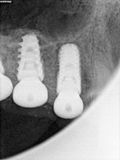

fredlibc | all galleries >> Galleries >> JGolo - urq implants > R9.jpg

R9.jpg